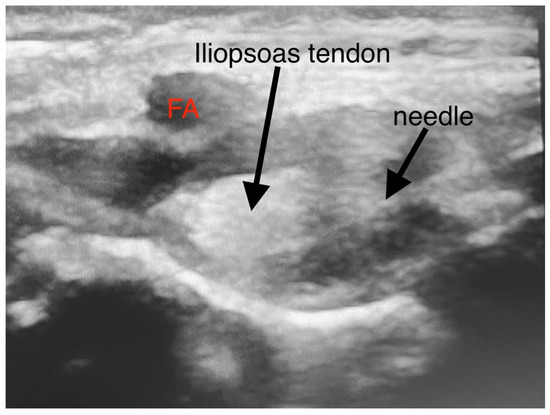

Figure 1.

Sonoanatomy of PENG. (FA-femoral artery; PE—pectineus muscle; AIIS—anterior inferior iliac spine; IPE—iliopsoas prominence).

The patients were kept supine during the focal block. A low-frequency linear transducer (2–5 MHz) was put in a transverse plane along the left anterior inferior iliac spine (AIIS) to identify the iliopsoas muscle, femoral nerve, and femoral artery (FA). The probe was then rotated counterclockwise to align with the pubic ramus to visualize the AIIS, iliopsoas prominence (IPE), FA, iliopsoas, and iliopsoas notch. Under direct vision, a 22-gauge 50 mm echo needle was advanced in the lateral-medial plane between the psoas tendon and the pubic ramus until the needle tip touched the IPE. The needle was withdrawn, and after negative aspiration, 0.2% ropivacaine was injected in incremental doses. Preparation and surgical positioning allowed for maximal time for block onset.